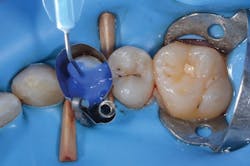

Figure 6: Applying phosphoric acid to tooth No. 5 in a total-etch approach

Figure 7: After thoroughly rinsing the etchant away, Prime&Bond Elect is scrubbed into the preparation for 20 seconds.

In this case, phosphoric acid was first applied to the margins of the preparation and then used to fill in the entire cavity (figure 6). After 15 seconds, the gel etchant was rinsed away and the preparation was left slightly moist. Prime&Bond Elect was scrubbed over the entire preparation, air-thinned for five seconds, and light cured for 10 seconds (figure 7). A bulk-fill flowable composite base was placed, followed by a hybrid composite restorative to fill the cavity per the manufacturer’s recommendations. The matrix and rubber dam were removed. After we checked occlusion and finished the restoration to achieve a smooth final surface, the patient was released (figure 8).